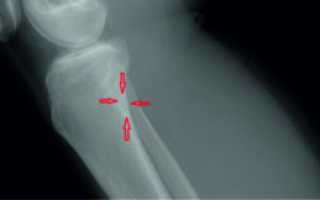

- Рентгенологическое обследование (рентген). Проводится для того, чтобы подтвердить диагноз. В данном случае проводится обследование сочленения в боковой проекции. На рентгеновском снимке видна остеохондропатия бугристости большеберцовой кости и ее фрагментация, если таковая имеется.